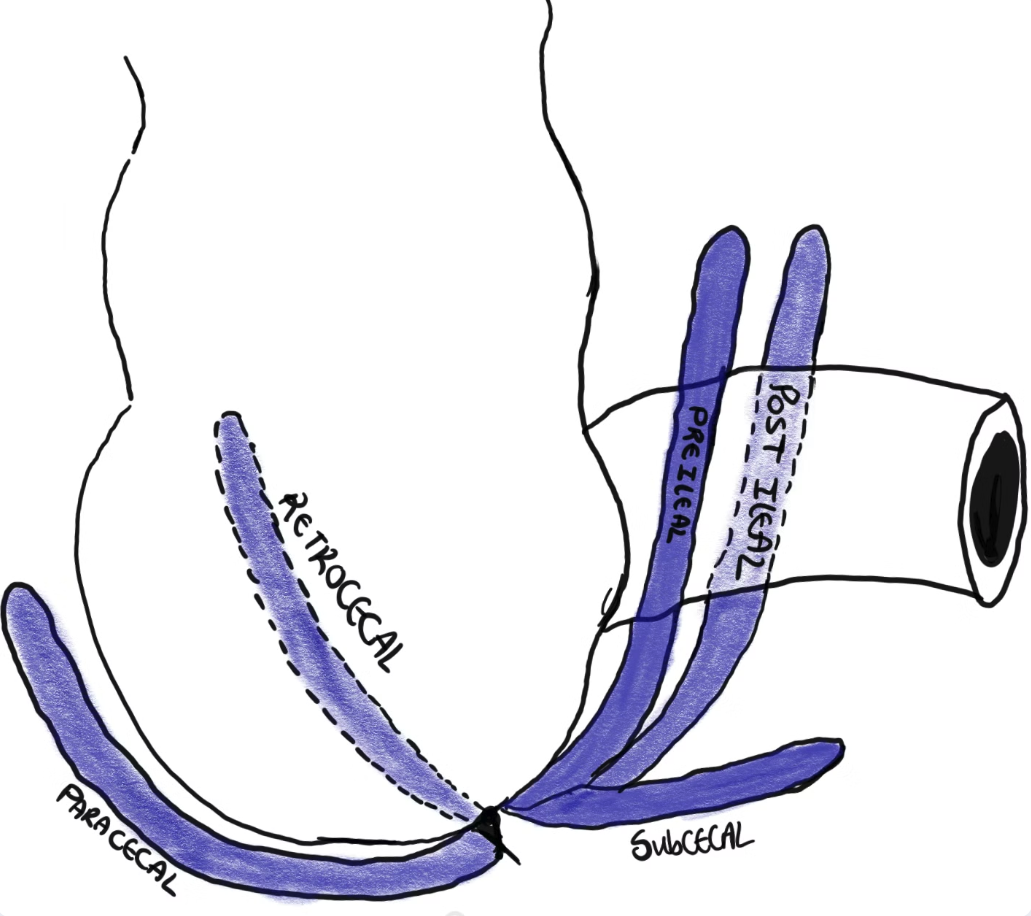

Positions Of The Appendix

This refers to the position of the free-end (or tip) of the appendix.

- The position of the appendicular orifice in the cecum (base) is consistent but the appendicular tip position is highly variable.

- This variability is due to the mobile nature of the surrounding bowel and the wide variation in length of appendix

- The position of the appendix can be in one of 7 positions, depending on the relationship of the appendix to the surrounding structures.

- The positions can be thought of the numbers on a clock face.

- Most common position is retrocecal (65% of the time).

a diagram showing different common positions of the appendix.

Positions of the appendix in relation to the terminal ileum

The appendix can be found in various positions relative to the ileum. These positions are typically described using a clock face analogy for easy reference:

Post ileal

This position is behind the ileum, corresponding to the 1 or 2 o’clock position.

Pre-ileal

In this position, the appendix is located in front of the ileum, also at the 1 or 2 o’clock position.

Para-ileal

Here, the appendix runs parallel to the Terminal ileum, represented by the 3 o’clock position.

Pelvic

In this position, the appendix extends inferiorly into the pelvis, corresponding to the 6 o’clock position.

Positions of the appendix in relation to the cecum

Retrocecal

This is the most common position, occurring in 65% of cases. The appendix sits posterior to the cecum, usually extending upwards behind it. It is found at the 11 o’clock position.

Subcecal

This position is on the inferior aspect of the cecum (not posterior to it!). It is located at the 8 o’clock position and occurs in 31% of cases.

Paracecal

In this position, the appendix is situated alongside the lateral border of the cecum, at the 10 o’clock position.

Clinical relevance

patient with appendicitis, with a retrocecal appendix can present with leukocytes and blood in urine. This happens due to irritation of the ureter by the surrounding inflammation. A positive urine dip does not always mean stones or UTI! Use your clinical judgement!!